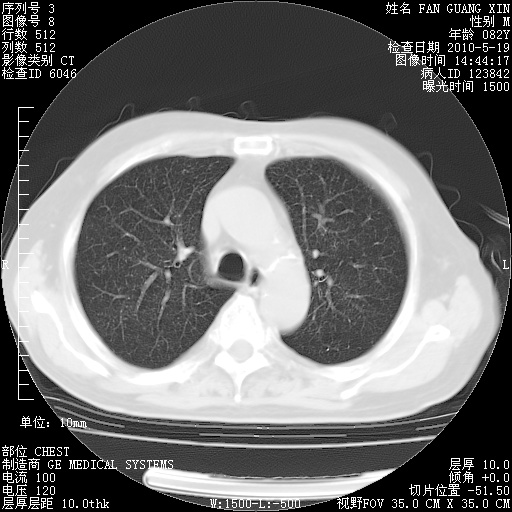

复查肺部CT,明显好转。为什么发热呢?

治疗3周后的肺部CT